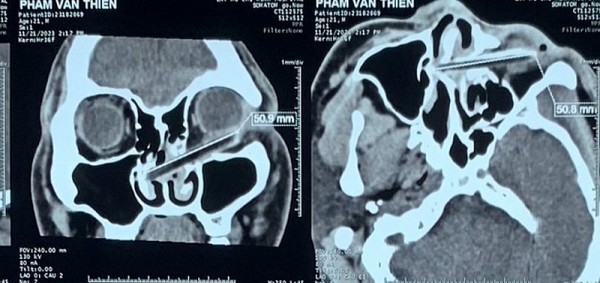

Chàng trai bị kẻ ngáo đá dùng đũa đâm xuyên hốc mắt khi đang đi trên đường

SKV - Ngày 29.11, Bệnh viện Tai mũi họng TP.HCM cho biết đã tiếp nhận nam bệnh nhân P.V.T (21 tuổi, ngụ Q.Bình Tân, TP.HCM) vì bị đâm chiếc đũa vào mắt, một phần đũa bị gãy nằm lại trong hốc mắt.